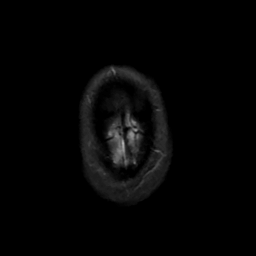

MR Study #6, March 17, 1991 -- Slice #48

[Home][Help][Clinical][Tour 1][Tour 2] Slice 48